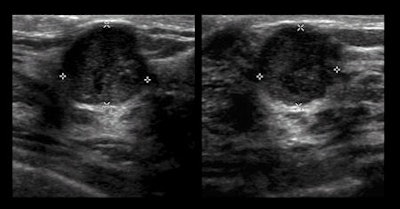

Ultrasound's benefit

There were 32 cancers (29%) that were discovered by ultrasound alone, while nine cancers (8%) were found exclusively by MRI after both mammography and ultrasound failed to detect the abnormalities. A total of 11 cancers (10%) were not detected by any of the three imaging modalities, including nine cancers (8%) detected clinically in the interval between screenings.

Supplemental ultrasound also increased cancer detection with each screening beyond mammography by uncovering an additional 5.3 cancers per 1,000 women in the first year and 3.7 more cancer cases per 1,000 per year in each of the second and third years of screening. Sensitivity for mammography plus ultrasound was 76%, specificity was 84%, and positive predictive value of biopsy was 16%.

Mammography alone achieved sensitivity of 52%, specificity of 91%, and positive predictive value of biopsy of 38%.